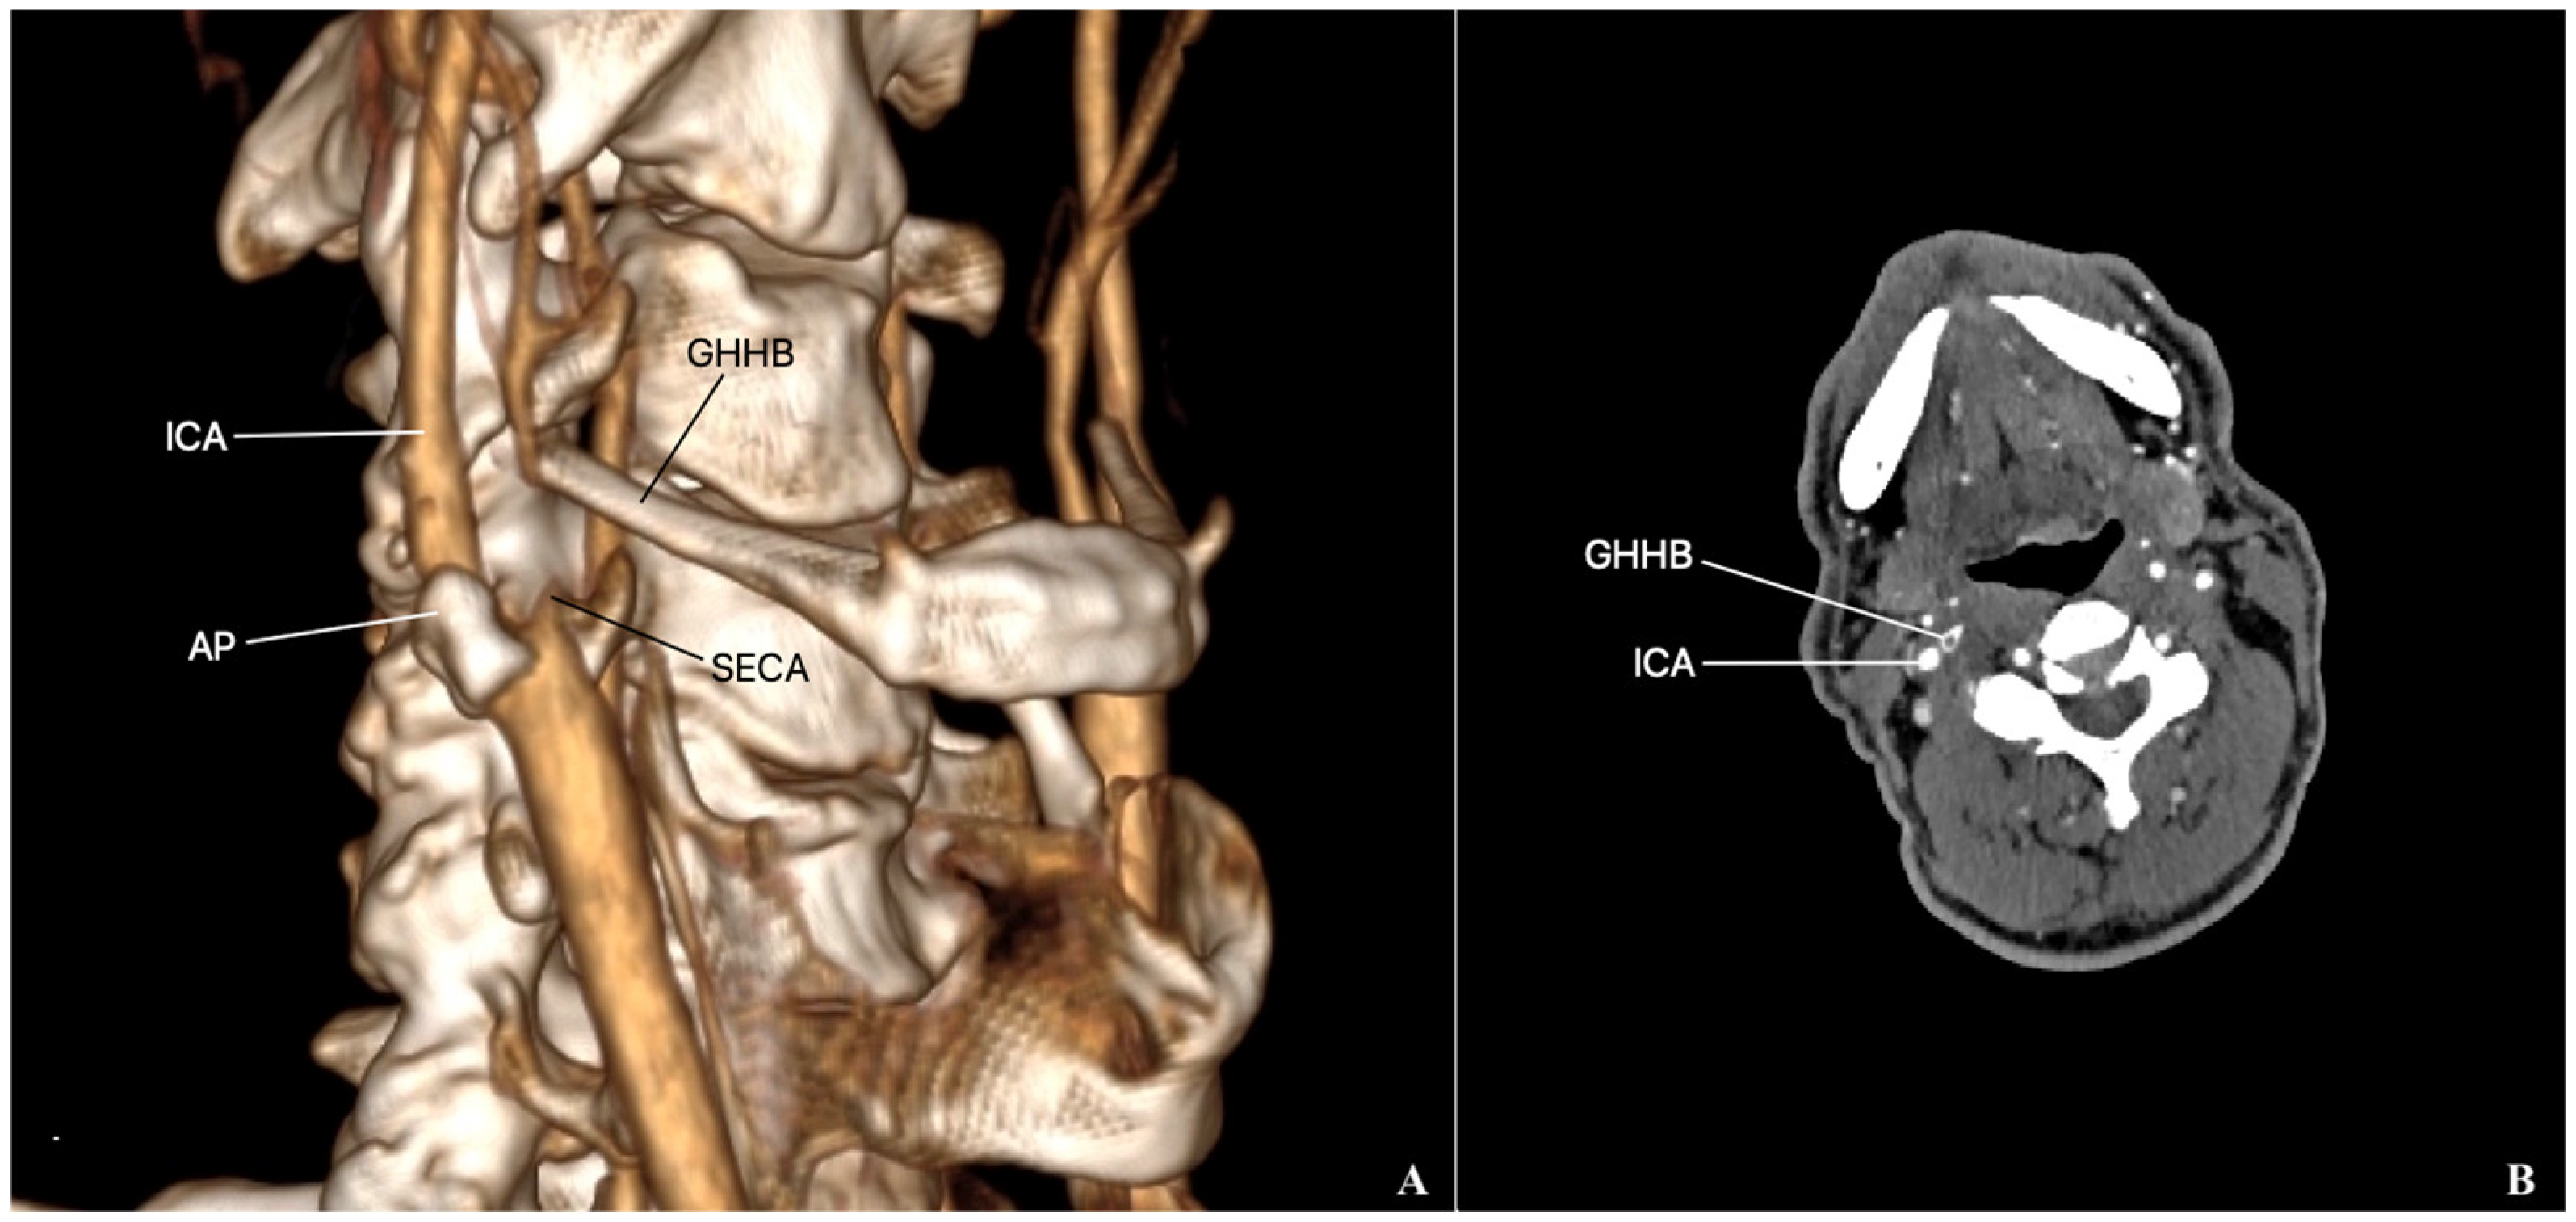

External Carotid Artery Entrapment by the Hyoid Bone Associated with an Atherosclerotic Stenosis of the Internal Carotid Artery

2. Case Presentation